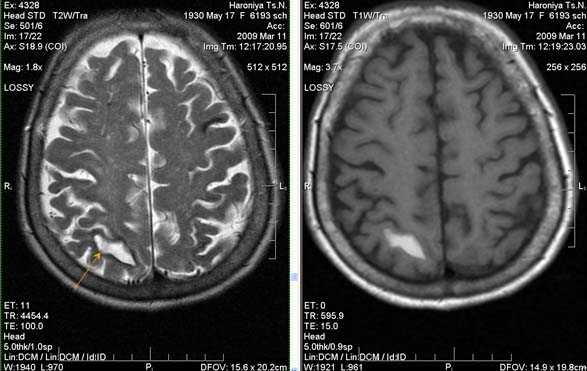

Характерным проявлением ДЭП на МР-томограммах является наличие множественных очагов глиоза.

В белом веществе левой лобной и обеих теменных долей, преимущественно субкортикально, выявлены множественные мелкие очаги хронической ишемии (большинство локализованных в бассейне правой средней мозговой артерии).

Проявлением хронической ишемии является также развитие выраженных дистрофических изменений белого вещества паравентрикулярной локализации - лейкоареоз.

Выраженные дистрофические изменения белого вещества паравентрикулярной локализации - лейкоареоз.

Сочетание мультифокальных очаговых изменений с диффузной кортикальной церебральной атрофией.